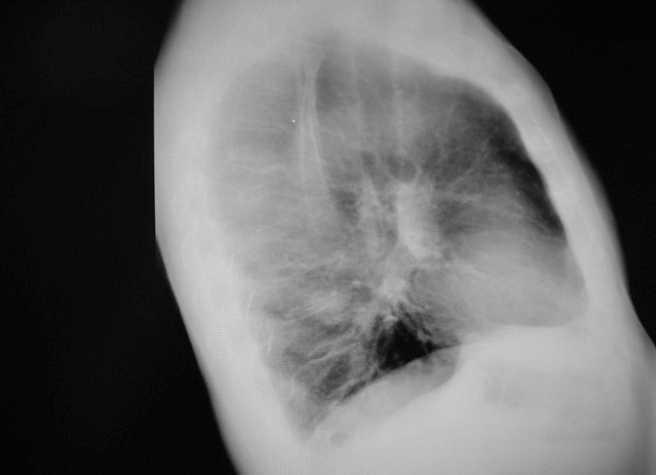

Conservative treatment began with ACE inhibitors and ARBs. At the fourth month of diagnosis, due to lack of response, CsA was started without success. After sixth month, the patient was switched to treatment with chlorambucil and prednisone for eight months with no response, and this treatment was suspended due to leukocytopenia. A year and a half after the biopsy, partial remission was reached (proteinuria: 5g/day) with conservative treatment. After two years, a node appeared in the left lower lung lobe (Figure). Fibre-optic bronchoscopy confirmed stage IV squamous cell carcinoma. Further analyses showed numerous nodules indicative of pleural, bone and liver metastases.

Figure 1. Lateral chest x-ray